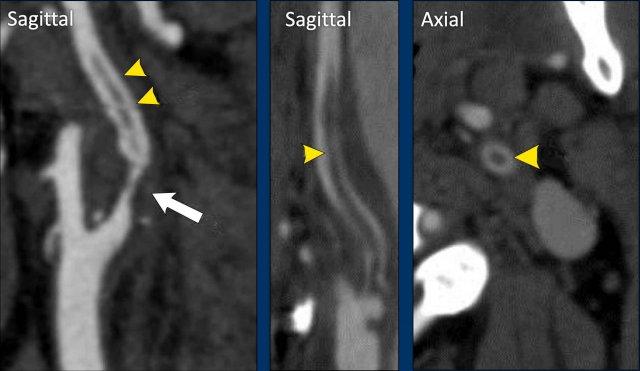

Trên CTA, hình ảnh bóc tách mạch máu biểu hiện với các dấu hiệu sau:

- Trên các lớp cắt ngang (axial), lòng mạch ICA bị hẹp và lệch tâm.

- ICA bị giãn rộng (↑ tổng đường kính).

- Phần phình cảnh (bulbus) không bị tổn thương, khác với bệnh lý xơ vữa động mạch.

- Bóc tách thường dừng lại trước khi đi vào hộp sọ.

Dấu hiệu sợi chỉ (String sign)

Trong hầu hết các trường hợp, bóc tách mạch máu sẽ biểu hiện với hình ảnh dạng ngọn lửa như trong hình A, nhưng khi lòng mạch bị chèn ép ít hơn và vẫn còn thông một phần, bạn có thể thấy “dấu hiệu sợi chỉ” như trong hình B.

Quan sát phía dưới nền sọ

Khi nghi ngờ khả năng bóc tách mạch máu, điều quan trọng là phải khảo sát các lớp cắt ngang ngay phía dưới nền sọ như trong trường hợp này.

Ở bên trái, ICA và ECA có hình ảnh bình thường (cấu trúc tăng tỷ trọng nằm giữa hai mạch là mỏm trâm).

Ở bên phải, chúng ta thấy ECA bình thường và phía trong tĩnh mạch cảnh là ICA bị giãn (vòng tròn).

Lòng mạch không ngấm thuốc cản quang.

Sự kết hợp giữa hình ảnh tắc nghẽn trong một ICA bị giãn và phình to cho thấy chúng ta đang đối mặt với một trường hợp bóc tách mạch máu.